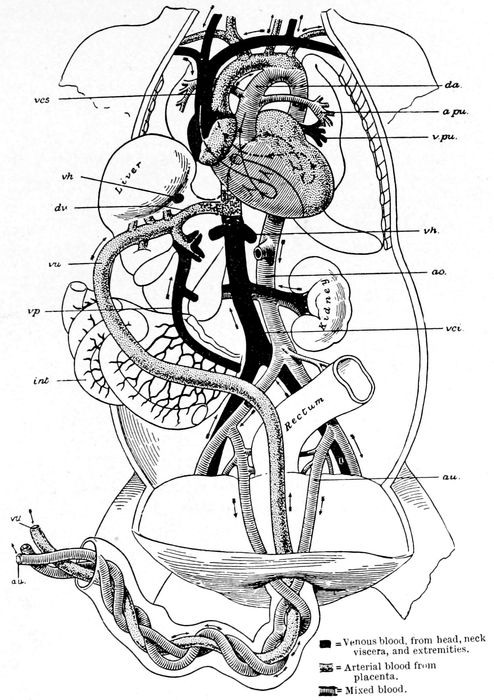

Fig. 23.—The fœtal circulation. (Edgar.)

The Fœtal Circulation.—The placenta is an organ

of nutrition as well as respiration, and through the

umbilical vessels the food materials are brought to the

fœtus and the waste products removed.

Surrounded by the jelly of Wharton that fills out the

cord, and running in and out between the two arteries,

the umbilical vein passes into the fœtal abdomen and divides

into two branches, one, the larger, short-circuits directly

into the inferior vena cava. This branch is called the

ductus venosus. The other joins the portal vein and

passes through the liver, after which it also enters the

vena cava.

Thus the heart is fed with a mixed blood, part coming

fresh from the placenta and part coming up from

the lower half of the fœtus. This blood is poured into

the right auricle, where it becomes mixed again with

the blood coming down from the upper pole of the fœtus

through the superior vena cava.

50Now a small part goes down into the right ventricle

and is forced into the pulmonary arteries to supply

the lungs. But the lungs are not functionating, hence

the greater part is again short-circuited through the ductus

arteriosus into the arch of the aorta, where it meets

with the great volume of blood which passed over into the

left auricle through the hole in the septum between the

right and left auricles, called the foramen ovale, thence

down into the left ventricle and out through the aorta to

supply the rest of the fœtal body.

With the exception of the ductus venosus and the

ductus arteriosus and the foramen ovale, the circulation

is the same as in the adult.

The blood in the descending aorta again divides and

part goes on to supply the lower extremities while the

greater part leaves the internal iliac arteries by means

of the hypogastric vessels and returns through the umbilical

arteries to the placenta for oxygenation.

As soon as the child is born, the fœtal structures are

altered. The child breathes, the pulmonary circulation

is established and the ductus arteriosus is closed. The

placental circulation is abolished, and the ductus venosus

and the hypogastric arteries are converted into solid

fibrous cords. Owing to the immediate change of pressure

in the auricles, the foramen ovale closes and the

circulation assumes the adult type.